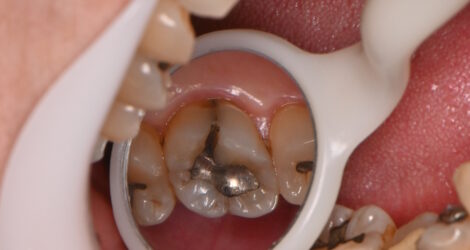

こんにちは歯科助手の毛利です! 今回はMTAセメントの症例をご紹介します🦷   こちらの患者様は30代男性で以前銀歯で治療したところの下に大きな虫歯が出来ていました。 虫歯を全て削り取ると、神経が露出してしまうので神経処置が必要です。 しかし、神経処置をした歯は平均して7.1年で抜歯の対象になります。 そのため、ご自 …